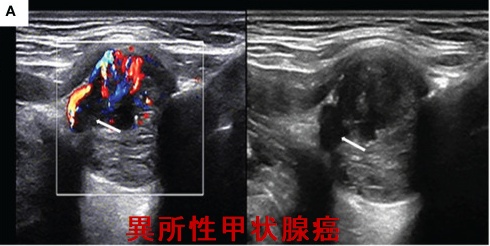

[写真、Front Oncol. 2022 Nov 18;12:1072607.より改変]

異所性甲状腺癌